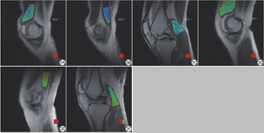

KOA组与对照组肌肉T2值比较分析显示:KOA组缝匠肌、半膜肌、股内侧肌、股二头肌、腓肠肌内侧头、腓肠肌外侧头的T2值均高于对照组(图1),差异均具有统计学意义(P<0.05;表1)。

肌肉T2 mapping伪彩图与解剖图的融合图像中,色阶信号由蓝到绿到红代表T2值逐渐升高。KOA患者WORMS升高,股内侧肌、缝匠肌、腓肠肌内侧头的T2值呈升高趋势(图1)。WORMS较低的KOA患者,肌肉内色阶以蓝色为主;WORMS高的KOA患者,肌肉T2伪彩图多呈现绿色或红色色阶为主,意味着肌肉T2值升高(图3)。